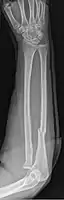

Galeazzi facture (displaced fracture of the radius)

- Galeazzi fracture - not a fracture of the ulna but a displaced fracture of the radius accompanied by a dislocation of the ulna at the wrist, where the radius and ulna come together.[2]